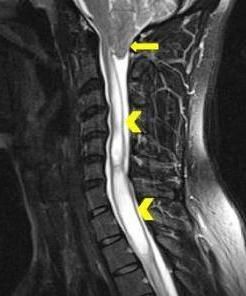

A 29-year-old man presented with a 4-year history of headache and severe neck pain. What does the cervical MRI scan without contrast reveal?

What does the cervical MRI scan without contrast reveal?